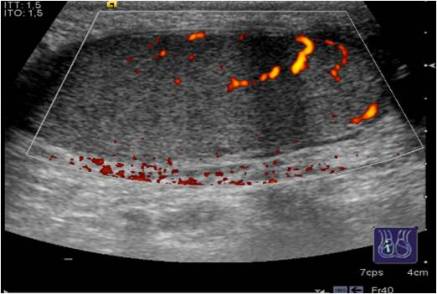

El Doppler presenta una alta sensibilidad para detectar vascularización tumoral.

Doppler